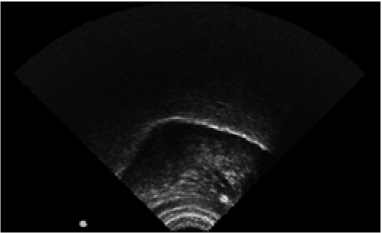

A sequence 2D Gray-scale images was obtained from the ultrasound system. One ultrasound image is shown in the figure 3. The most relevant information shown in the image is the tongue contour. Therefore, it was necessary to process the images for extraction of the tongue contour from each ultrasound image. For this purpose, we used the software EdgeTrak [21]. The procedure is carried out as follows: first, each ultrasound image is loaded into the software, then the area of interest is adjusted (where the contour of the tongue is located). In figure 4 is shown the area of interest as the green window. Then the contour must be initialized with 6 points along the tongue and finally the software applies an algorithm based on active contours [22] which allows to obtain the complete contour. In this final step and similar to [11], we observed that in practice the algorithm lost the track of the tongue frequently. For that reason, it was necessary to verify frame by frame visually, and when necessary, to correct the contours manually. Thus, we adopted a semi-automatic approach. This process is time-consuming and it is not commonly carried out in speech ultrasound databases. In the figure 4 it can be seen an example of the contour extracted from an ultrasound image. Each tongue contour is exported in a text file, which contains a matrix with the contour coordinates (xm,ymsubscript𝑥𝑚subscript𝑦𝑚x_{m},y_{m}) and where m={1,2,,50}𝑚1250m=\{1,2,...,50\} correspond the number of points extracted.

Refer to caption

Figure 3: One 2D Ultrasound Tongue Image recorded.